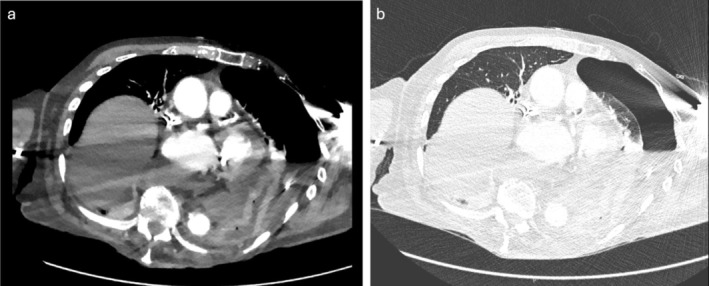

一名95岁女性因胸痛和呼吸困难就诊于急诊科。她有左侧紧张性气胸,继发于靠近胃-食管交界处的裂孔疝自发性破裂。这在以前的文献中没有描述过,因此,本报告的目的是引起临床医生的兴趣,并强调这种罕见的现象作为胸痛的裂孔疝患者的可能鉴别诊断。这也证明了在使用计算机断层扫描检查食管破裂时使用口服造影剂的重要性。

A 95-year-old female presented to the emergency department with chest pain and difficulty breathing. She had a left-sided tension hydropneumothorax secondary to a spontaneous rupture of a hiatus hernia close to the gastro-oesophageal junction. This has not previously been described in the literature and therefore, the purpose of this report is to pique clinicians' interest and highlight this rare phenomenon as a possible differential diagnosis in patients with a hiatus hernia who present with chest pain. It also demonstrates the importance of the use of oral contrast when using computerised tomography to investigate for oesophageal rupture.